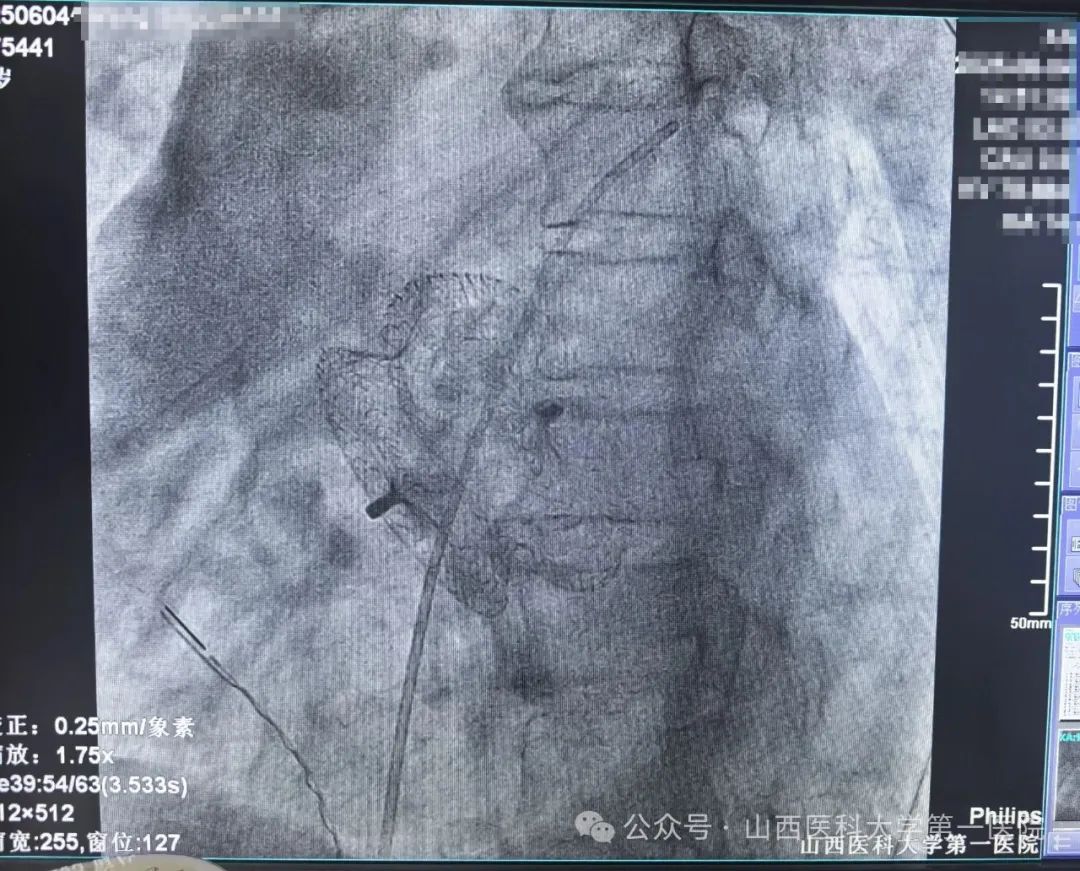

次日,通过超声影像科经食道超声再次精确评估,明确患者房缺缺损直径达37mm,肺动脉压65mmHg。一般临床中通过介入封堵的最大房缺为36mm以下,否则需要外科开胸来进行房缺修补,但患者心衰症状刚刚改善,身体整体状态欠佳,患者及家属对开胸手术存在很大顾虑。电生理团队经过评估后认为患者虽然巨大房缺,但各残缘情况尚可,存在介入封堵的可能,并结合技术优势可以在心腔内超声辅助下指导封堵伞的释放,再次与患者及家属沟通后决定采用射频消融+房缺介入封堵一站式微创手术方案,王睿主任医师团队顶着高难度高风险的压力为患者实施了三维标测下房扑射频消融术+房间隔缺损封堵术。术中,在可调弯长鞘的辅助下精细标测确定患者房扑为围绕三尖瓣峡部折返的典型房扑,三尖瓣峡部电隔离后患者房扑终止,恢复窦性心律;接下来,在心腔内超声指导下,选择42mm大封堵伞进行精确释放,成功封堵巨大房缺。封堵前后患者血氧明显改善,肺动脉压无进一步升高,观察二十分钟,患者无不适,反复牵拉实验示封堵伞位置稳定,遂释放封堵伞,完成手术。术后第三天复查心脏超声,显示封堵器位置固定,未见穿隔分流。